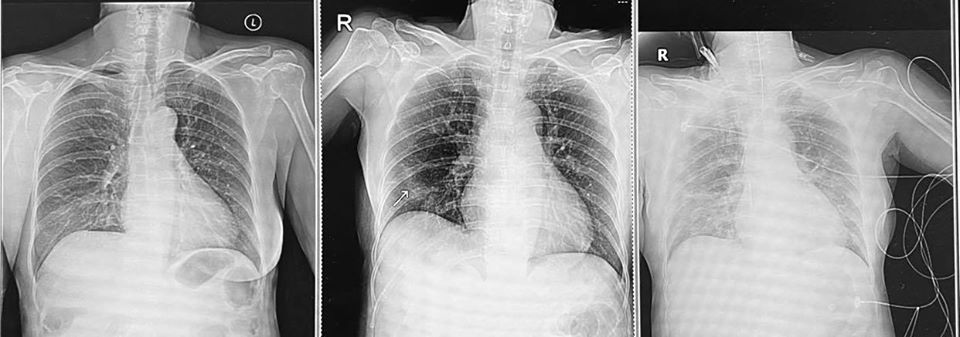

อย่างไรก็ตาม เมื่อเธอเริ่มมีอาการเหมือนเป็นหวัด ถึงเริ่มแยกตัวจากคนในบ้าน แต่ก็ไม่ทันเสียแล้ว เมื่อแม่ของเธอกลับมีอาการปอดอักเสบ ระบบหายใจล้มเหลวอย่างรวดเร็วจนต้องใส่ท่อช่วยหายใจ และย้ายเข้าห้องไอซียู อาการโคม่าอยู่ในขณะนี้